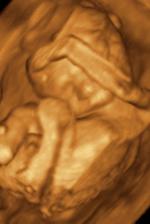

♥ dne 18.9. 3D UTZ - s manželem jsme si móóóc užívali, mrňousek je úúúžasný, takový skříteček..., ale náš 🙂